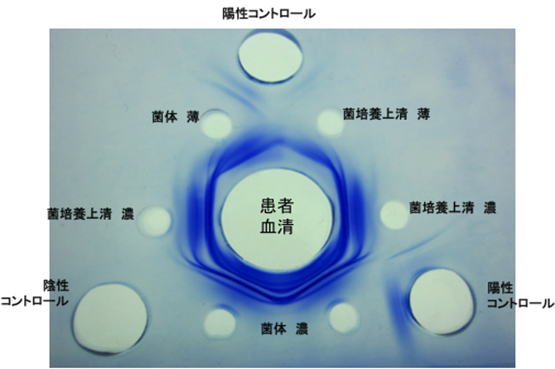

免疫力のない方で問題となる真菌(アスペルギルス感染症)(図7, 8)やニューモシスチス肺炎(図9)に対しては、当科研究室独自に抗体検査や核酸増幅検査を行い、迅速な診断・治療に努めております。国内の研究・検査機関とも協力し、稀な真菌・抗酸菌感染症についても、病原体の同定・診断を試みております(図10) 。

図7. アスペルギルスの沈降抗体。患者血清とアスペルギルス(菌体あるいは培養上清)との間に、沈降抗体の存在を示す沈降線が六角形として認められます。